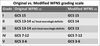

What are the two commonly used scales for SAH grading

Fisher grading (Modified fisher)

WFNS

Features of Fisher grading

Use the amount of blood seen on CT to predict the subsequent risk of radiological vasospasm.

1-4.

Issues with original Fisher grading

Used an early CT scanner with images printed on films. Measured manually with rulers, theefore measurements only apply to images obtained on scanner.

Patients could also be classified into more than one grade

Fisher 1

No blood on CT scan